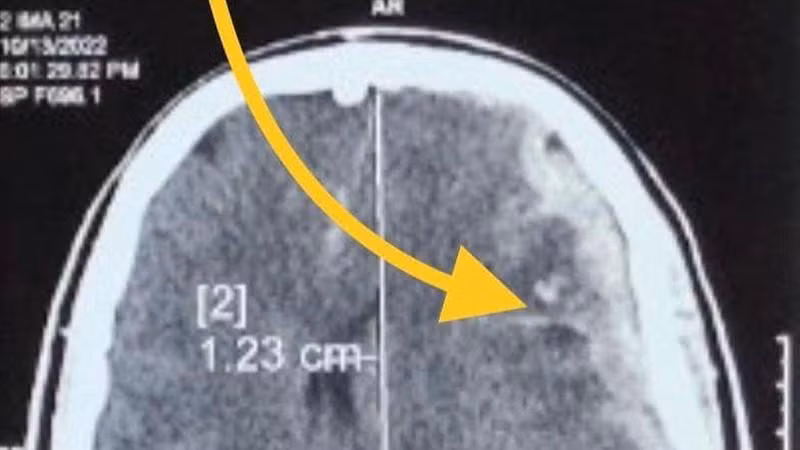

| Hình ảnh cho thấy bệnh nhân bị tổn thương não. Ảnh: BV. |

Trường hợp thứ 2 là một nữ bệnh nhân 48 tuổi, bị ngã cao 3 mét tại công trường xây dựng mà không có bảo hộ. Sau tai nạn, được đưa vào cấp cứu ngay giờ thứ 2 tại Bệnh viện Trung ương Quân đội 108 với tình trạng lơ mơ, ý thức xấu dần, chảy máu tai bên phải.

Bệnh nhân được nhanh chóng xử trí sơ cứu, chụp cắt lớp vi tính phát hiện chảy máu não lớn bán cầu não trái chèn ép não, vỡ xương đá bên phải. Do vậy, bệnh nhân được phẫu thuật lấy máu tụ giải chèn ép não.